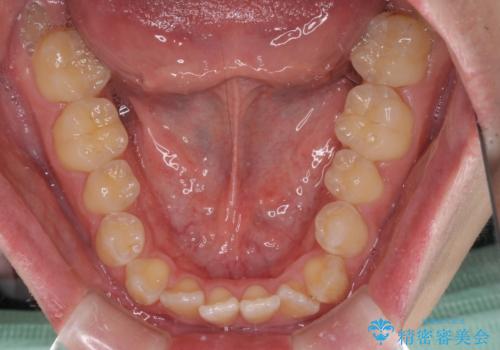

- 上下前歯のデコボコを気にして来院された患者様です。

ワイヤー矯正でもマウスピース矯正でも可能でしたが、短期間で、自身の手を煩わせることなく治療を行いたいとのことで、ワイヤー装置にて矯正治療を行うこととしました。